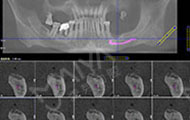

2016年10月 多颗牙缺失,敲定种牙方案

拍摄了CT,牙齿哪个地方有问题,看的很清楚,非常科学。但是口内有牙周病,需要先治疗再进行种牙,而且他们服务特别好,等待的时候还给倒水,安抚我让我感到很亲切,做了口内全口洁牙+喷砂+抛光+上药去除牙结石,是两个护士给洗的牙,一个细节就能提现这个机构好不好,卫生、环境方面都很不错,我也希望可以早点治疗好,做种植牙!